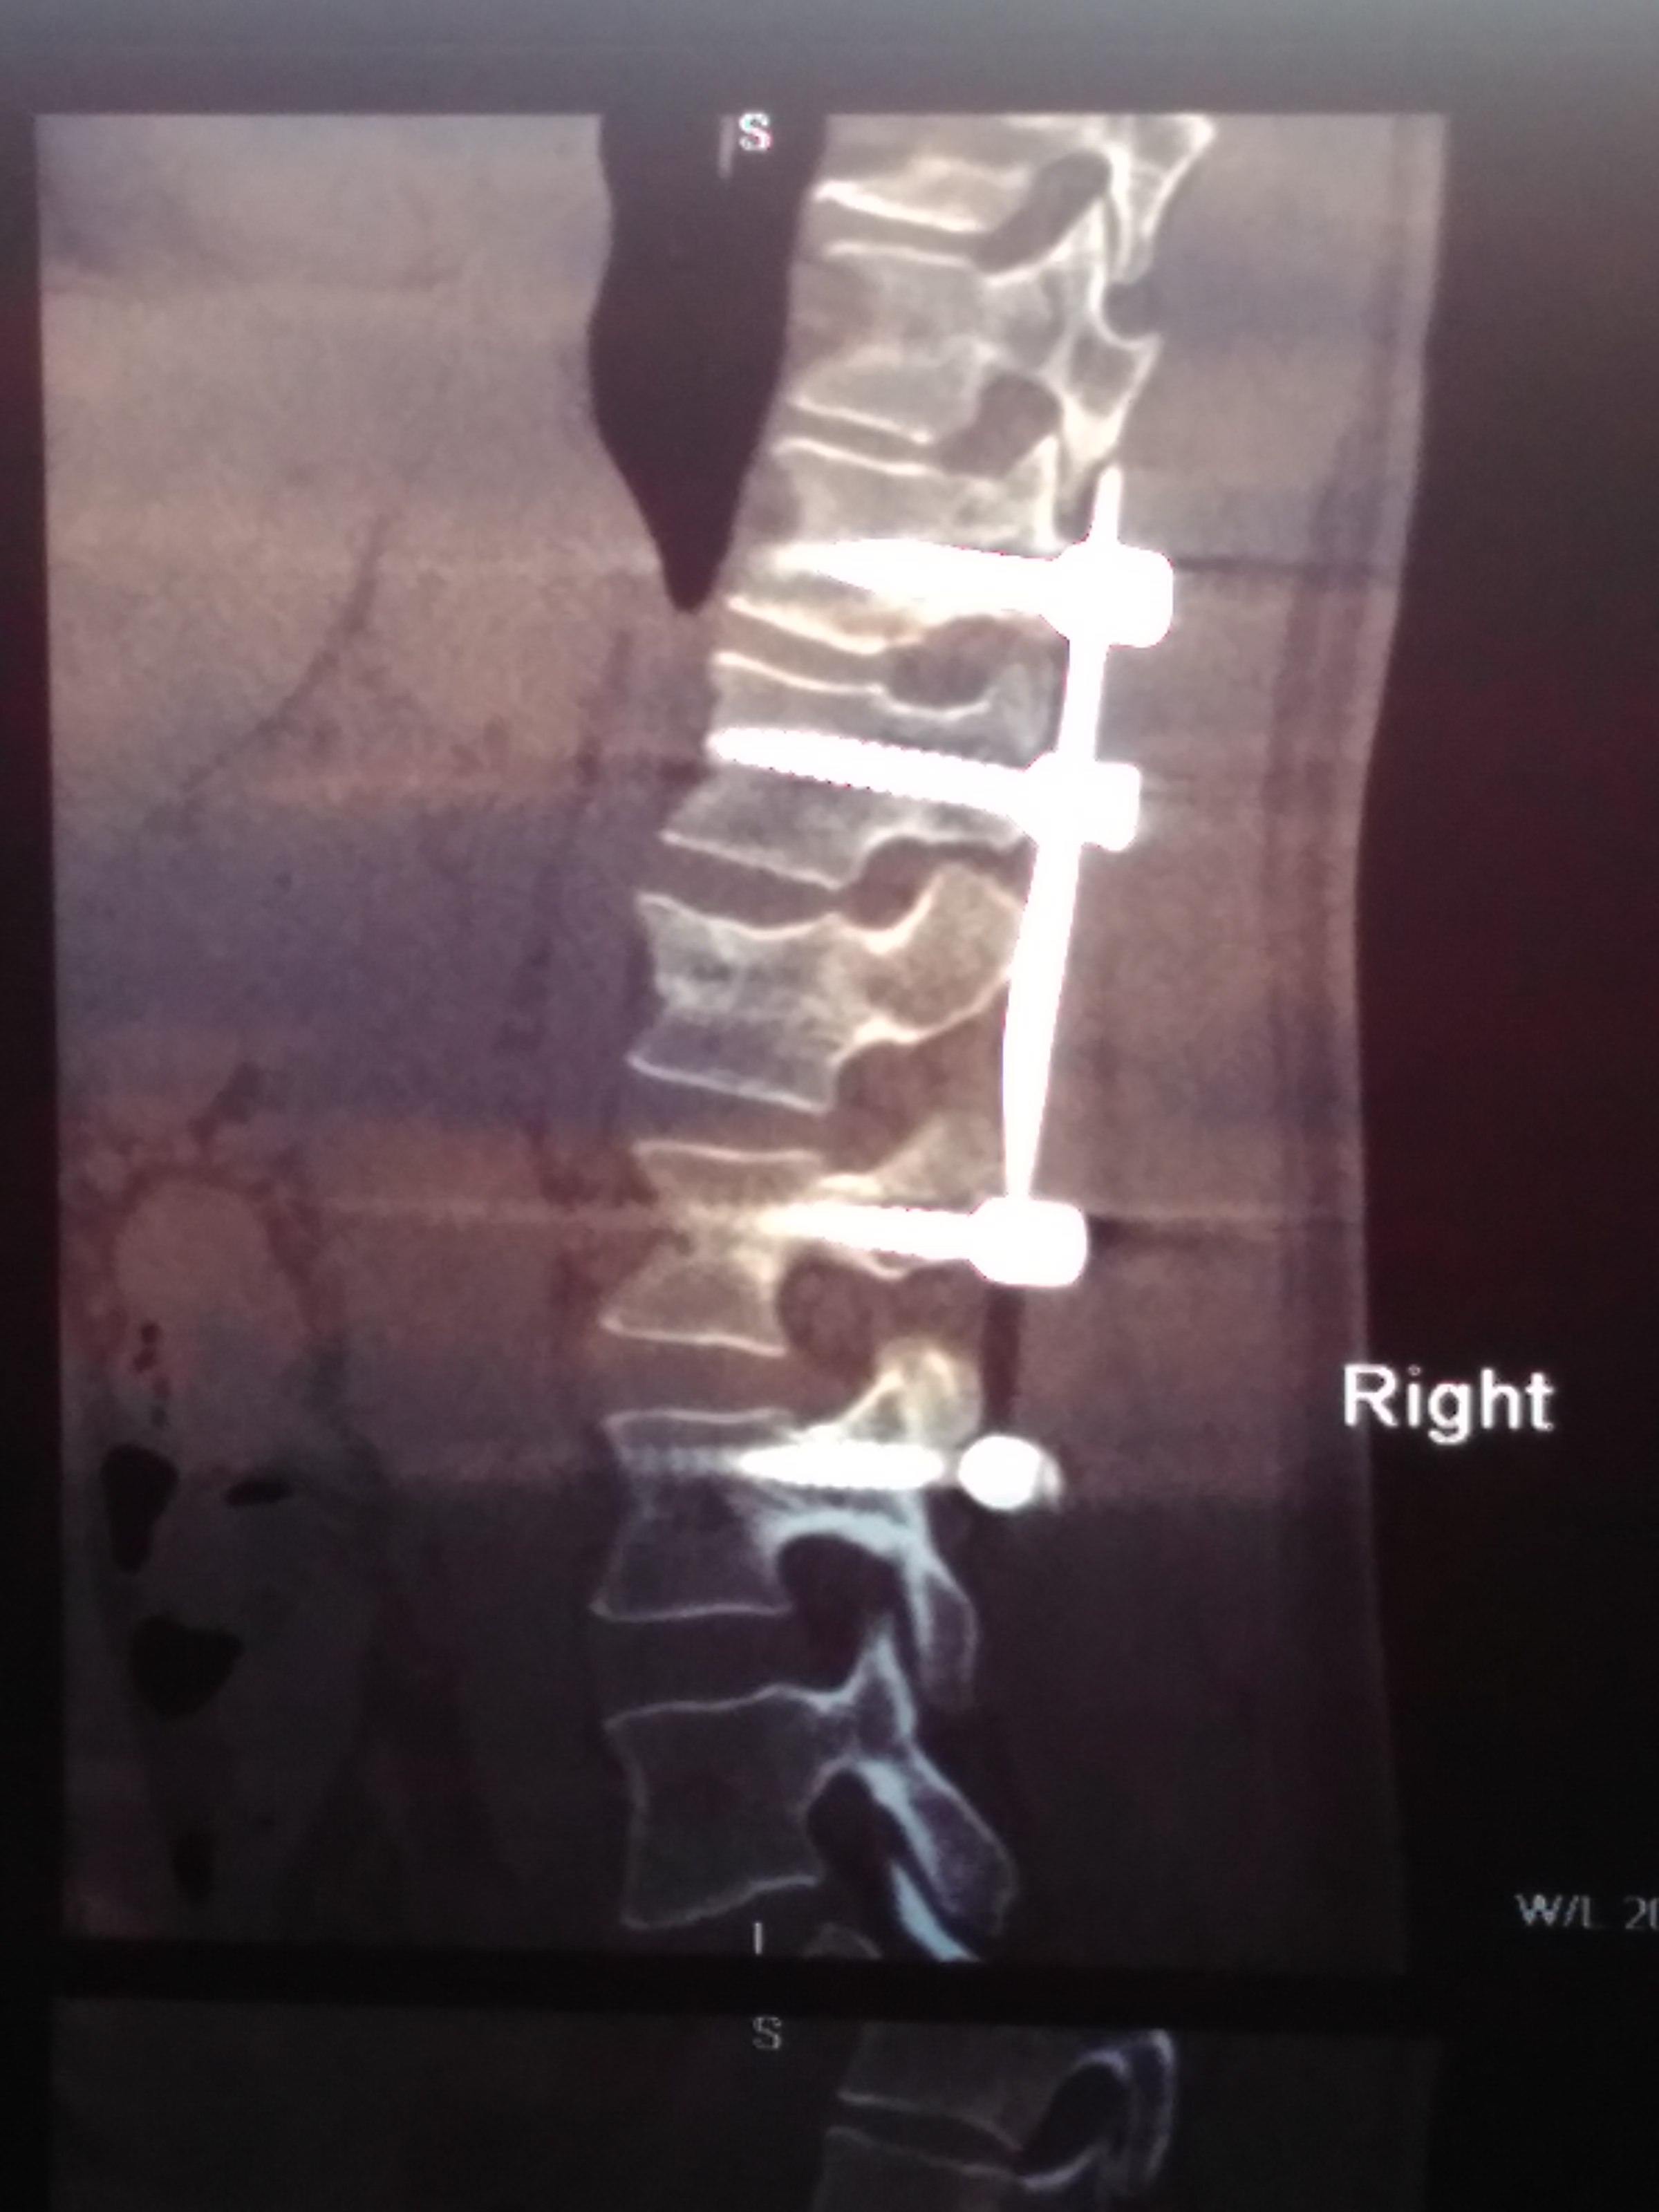

20 мая в результате падения с высоты получил взрывной перелом L1 типа В3, полное вертикальное и горизонтальное расщепление со смещением отломков задне-верхнего угла до 3,5 мм и переднего до 4,5 мм. А также вертикальный перелом Th12 типа В2 без смещения и расщепления. Через 5 дней была проведена операция ТПФ Th11,12-L2,3

7 августа (через 2,5 месяца) была сделана повторное КТ (снимки которого прикладываю). Со слов оперирующего доктора позвонок L1 не срастается, мелкие осколки "растворились", требуется операции по замене L1. В описании написано: частичный остеолиз краев фрагментов, с наличием диастазов до 5-6 мм.

12.jpg

11.jpg

01.jpg